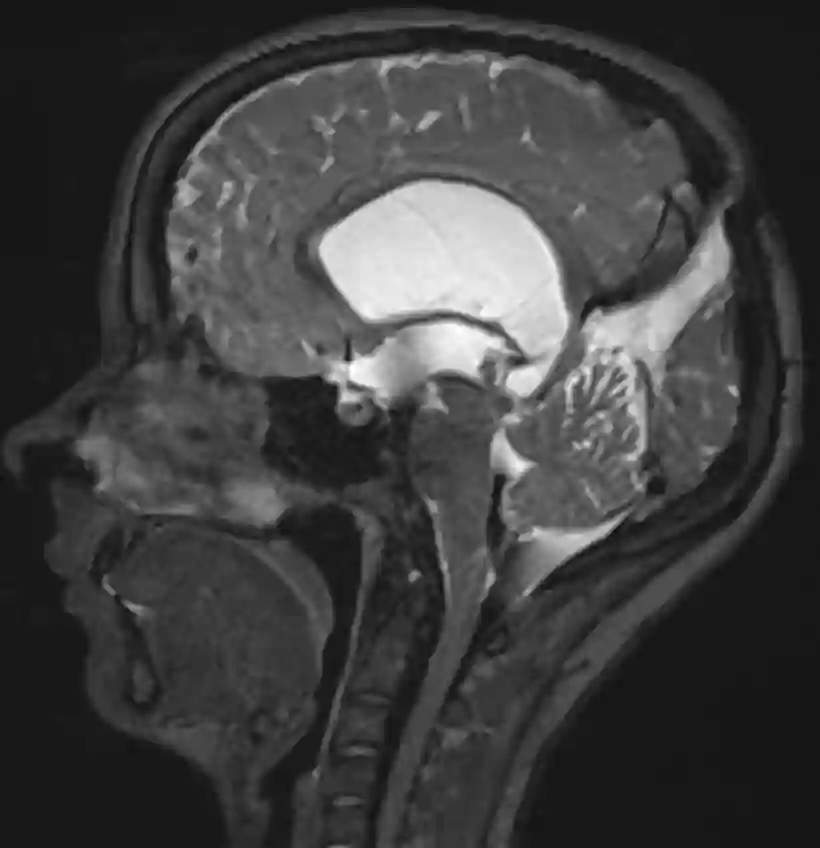

Sagittales T2 MRT Bild eines Patienten mit einer Balkenagenesie.

Die Balkenagenesie ist eine angeborene Fehlbildung des Gehirns, die dadurch gekennzeichnet ist, dass die Verbindung zwischen der rechten und linken Hirnhälfte, das Corpus callosum, fehlt.